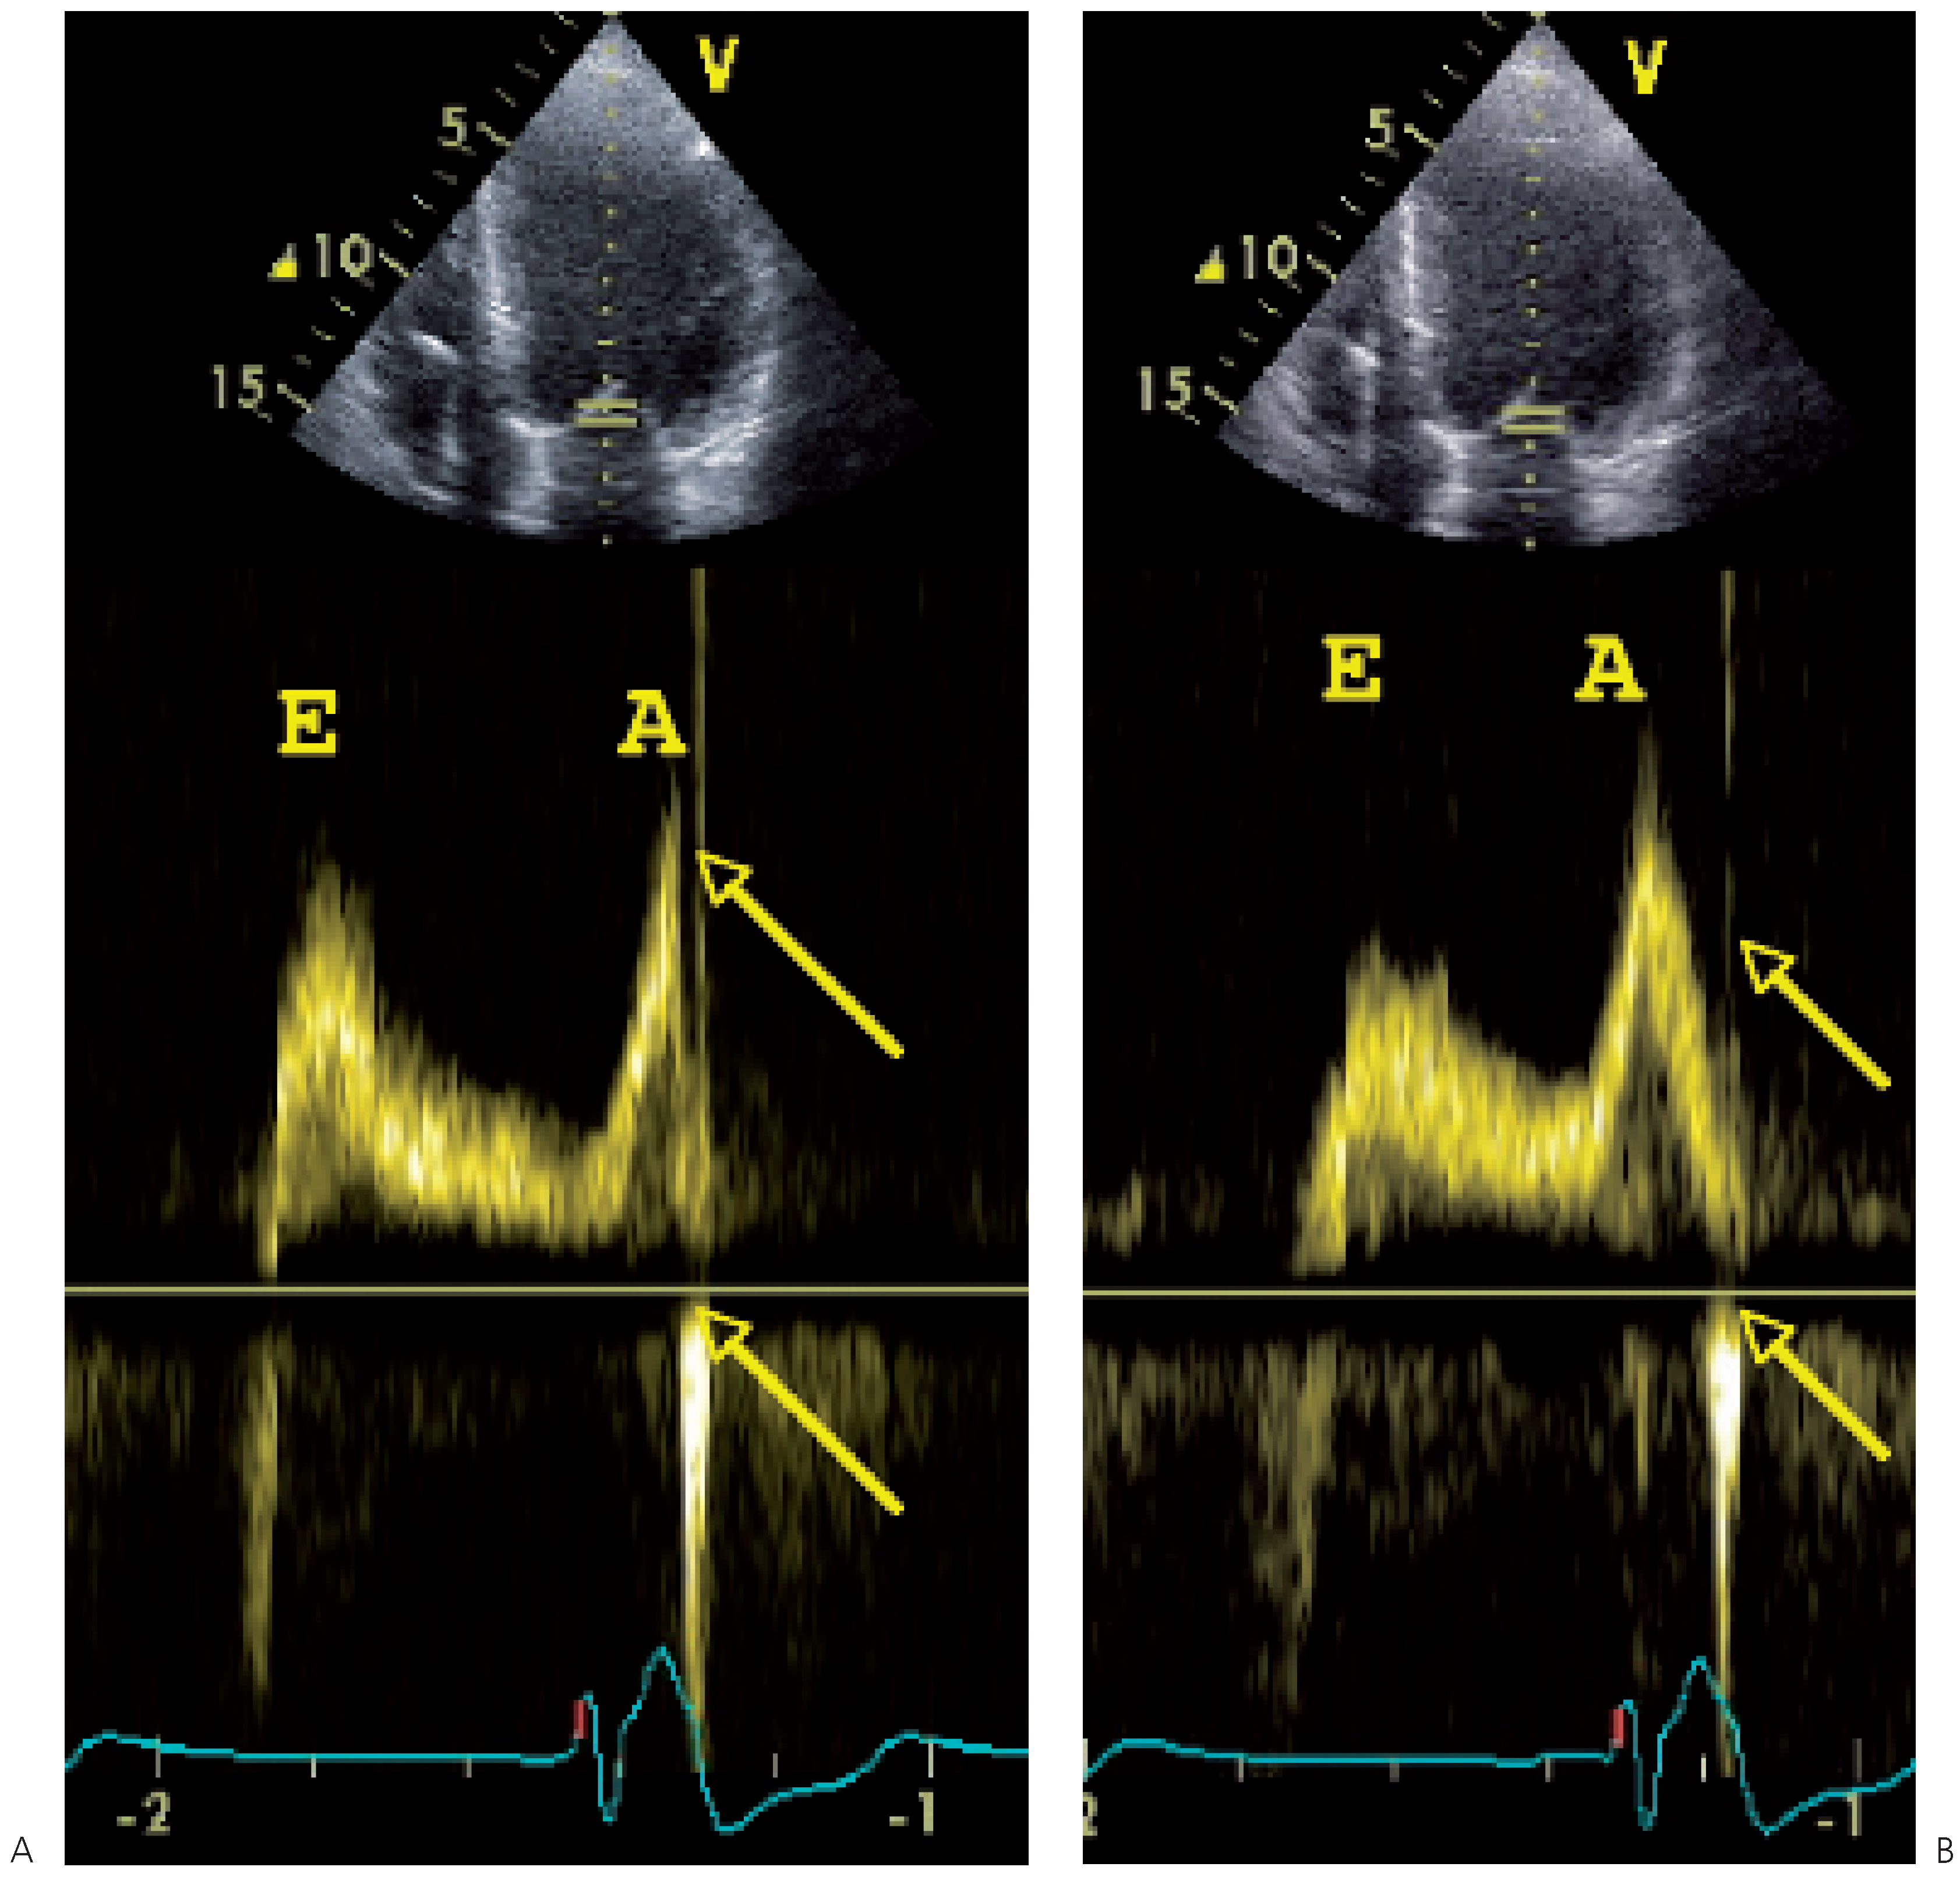

- Optimisation du délai atrioventriculaire